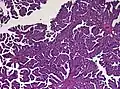

Histopathology

The tumor is neuroectodermal in origin and similar in structure to a normal choroid plexus. They may be created by epithelial cells of the choroid plexus. Papillary fronds lined by bland columnar epithelium are visible under the microscope. Normal absences include mitotic activity, nuclear pleomorphism, and necrosis.[10] Tumors have positive immunohistochemistry for cytokeratin, vimentin, podoplanin, and S-100.[11] Up to 20% of choroid plexus papilloma patients may test positive for glial fibrillary acidic protein (GFAP).[12] Studies have found that fourth ventricle cancers express more S100 than lateral ventricle tumors, and older patients (over 20 years) express more GFAP and transthyretin than younger patients.[13] Some individuals with choroid plexus papilloma have germline TP53 gene mutations, according to genetic analyses.[14] These cancers rarely exhibit nuclear p53 protein positivity. Aicardi syndrome, hypomelanosis of Ito, and 9p duplication are syndromic correlations of choroid plexus papilloma.